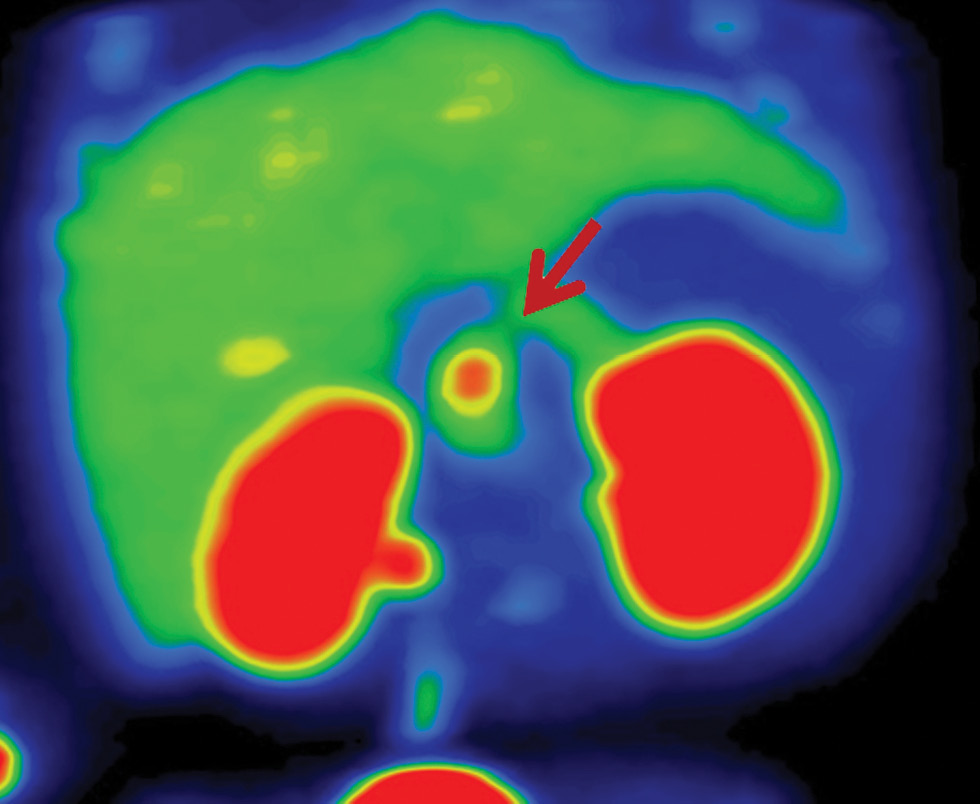

Учитывая принципиальные различия в объеме оперативного вмешательства, пациентам с фармакорезистентным течением ВГИ показано проведение ПЭТ с 18F-ДОФА. Визуализация поджелудочной железы происходит за счет захвата островковыми клетками радиоизотопа [18, 19]. В мировой литературе предлагается применение математического показателя ПИ для оценки результатов ПЭТ. При значении ПИ более 1,5 устанавливается фокальная форма, при значении ПИ менее 1,3 диагностируется диффузная форма ВГИ [20]. Однако на практике существуют определенные затруднения при применении данного параметра для дифференциальной диагностики морфологических форм. В нашем исследовании, несмотря на гистологически подтвержденную фокальную форму, у 1/3 пациентов значение ПИ было менее 1,5. Фокальная форма ВГИ по результатам ПЭТ у данной группы пациентов была предположена исходя из визуальных данных (рис. 3). Значение ПИ было максимальным в промежутках через 20–60 мин после введения радиоизотопа. Таким образом, вызывает сомнения необходимость проведения сканирования через 10 мин после исследования. Затруднения в применении ПИ могут возникнуть за счет физиологического повышенного захвата 18F-ДОФА в области головки поджелудочной железы, при оценке гигантских фокусов или мультифокусов [21, 22].

Рис. 3. Результаты ПЭТ/КТ с 18F-ДОФА у пациентов с различными морфологическими формами ВГИ.

а – диффузная форма ВГИ. Захват 18F-ДОФА равномерен; б – фокальная форма ВГИ. Визуализируется очаг накопления радиофармпрепарата; в – эктопическая локализация фокальной формы ВГИ. Очаг накопления радиоизотопа визуализируется в области двенадцатиперстной кишки.